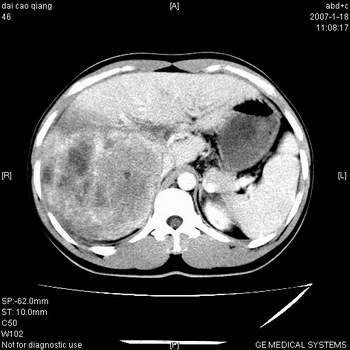

符合巨块型肝癌表现:

1、平扫低密度,增强后表现为快进快出。

2、动脉期可见迂曲的动脉供血血管

3、并可见门静脉右支癌栓形成

4、可见假包膜

5、腹主动脉旁结节影,考虑肿大淋巴结。

肝右叶巨块型肝癌,伴瘤栓形成,肿瘤有包膜,可见动静脉短路。

肝右叶巨大不均匀低密度肿块,前缘有假包膜,增强明显的呈快进快出表现,门脉右支有癌栓,病人虽然年轻但还是首先考虑肝右叶巨块形肝癌,病人血象高只能说有合并感染。不支持肝脓肿。